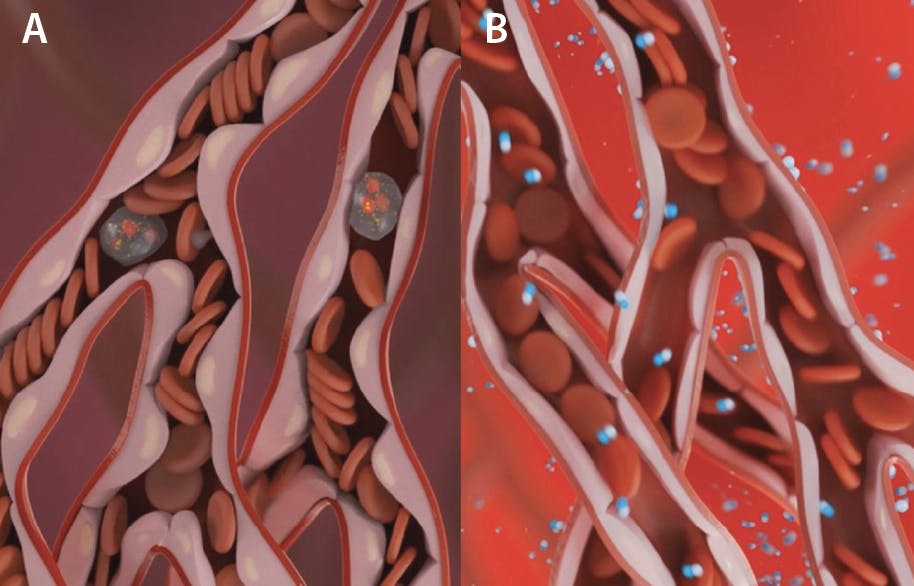

Reperfusion after restoration of epicardial coronary flow by percutaneous coronary intervention (PCI) is typically heterogeneous within the infarct zone, and significant areas of “low or no reflow” can be identified where perfusion is reduced.4 If the flow limitation is severe enough and long enough, it has the potential to ultimately extend the size of the infarction. Several factors may contribute to the “low or no reflow” phenomenon, including microvascular obstruction (MVO) due to debris released downstream during PCI and microvascular dysfunction caused by ischemia-induced endothelial edema (Figure 1A).

Figure 1. MVO post-PCI for STEMI. Endothelial swelling and neutrophils plugging blood flow (A). Dissolved oxygen in the microvasculature via SSO2 therapy reduces endothelial swelling and restores flow (B).

SSO2 therapy was initially conceptualized and developed by Dr. J. Richard Spears, et al to address myocardial salvage in STEMI.5,6 He developed a catheter-based approach of increasing the partial pressure of oxygen of coronary blood to very high levels (760-1,000 mm Hg) with the intention of increasing oxygen delivery to endothelial cells and myocardial tissue via diffusion through plasma. The hypothesis was that improved oxygenation may both salvage myocardial cells on the verge of dying and reverse endothelial swelling to relieve MVO; the latter further enhancing oxygen delivery by improved microvascular blood flow (Figure 1B). Several preclinical studies confirmed these hypotheses, specifically showing that compared to reperfusion with normoxemic blood reperfusion SSO2 therapy was associated with reduced capillary endothelial swelling; improved regional myocardial blood flow measured with radioactive microspheres (0.92 vs 0.43 mL/g/min)5; smaller infarct size, expressed as percent area of necrosis divided by area at risk (< 20% vs 70%-80%)6; and significantly better recovery of left-ventricular (LV) ejection fraction (EF) by approximately 20% absolute.5,6 Taken all together, these preclinical data supported the hypothesis of MVO contributing importantly to infarct size and recovery of LV function in AMI and that SSO2 is a therapy that successfully addresses this mechanism, opening the door to clinical trials.